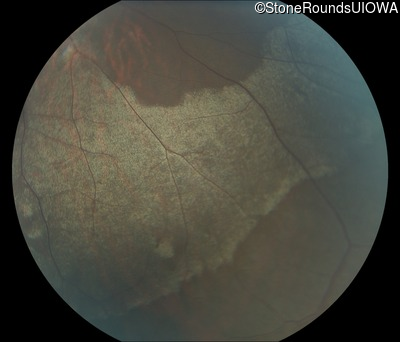

Fundus Montage - Right - 20/25 -3

Exemplar